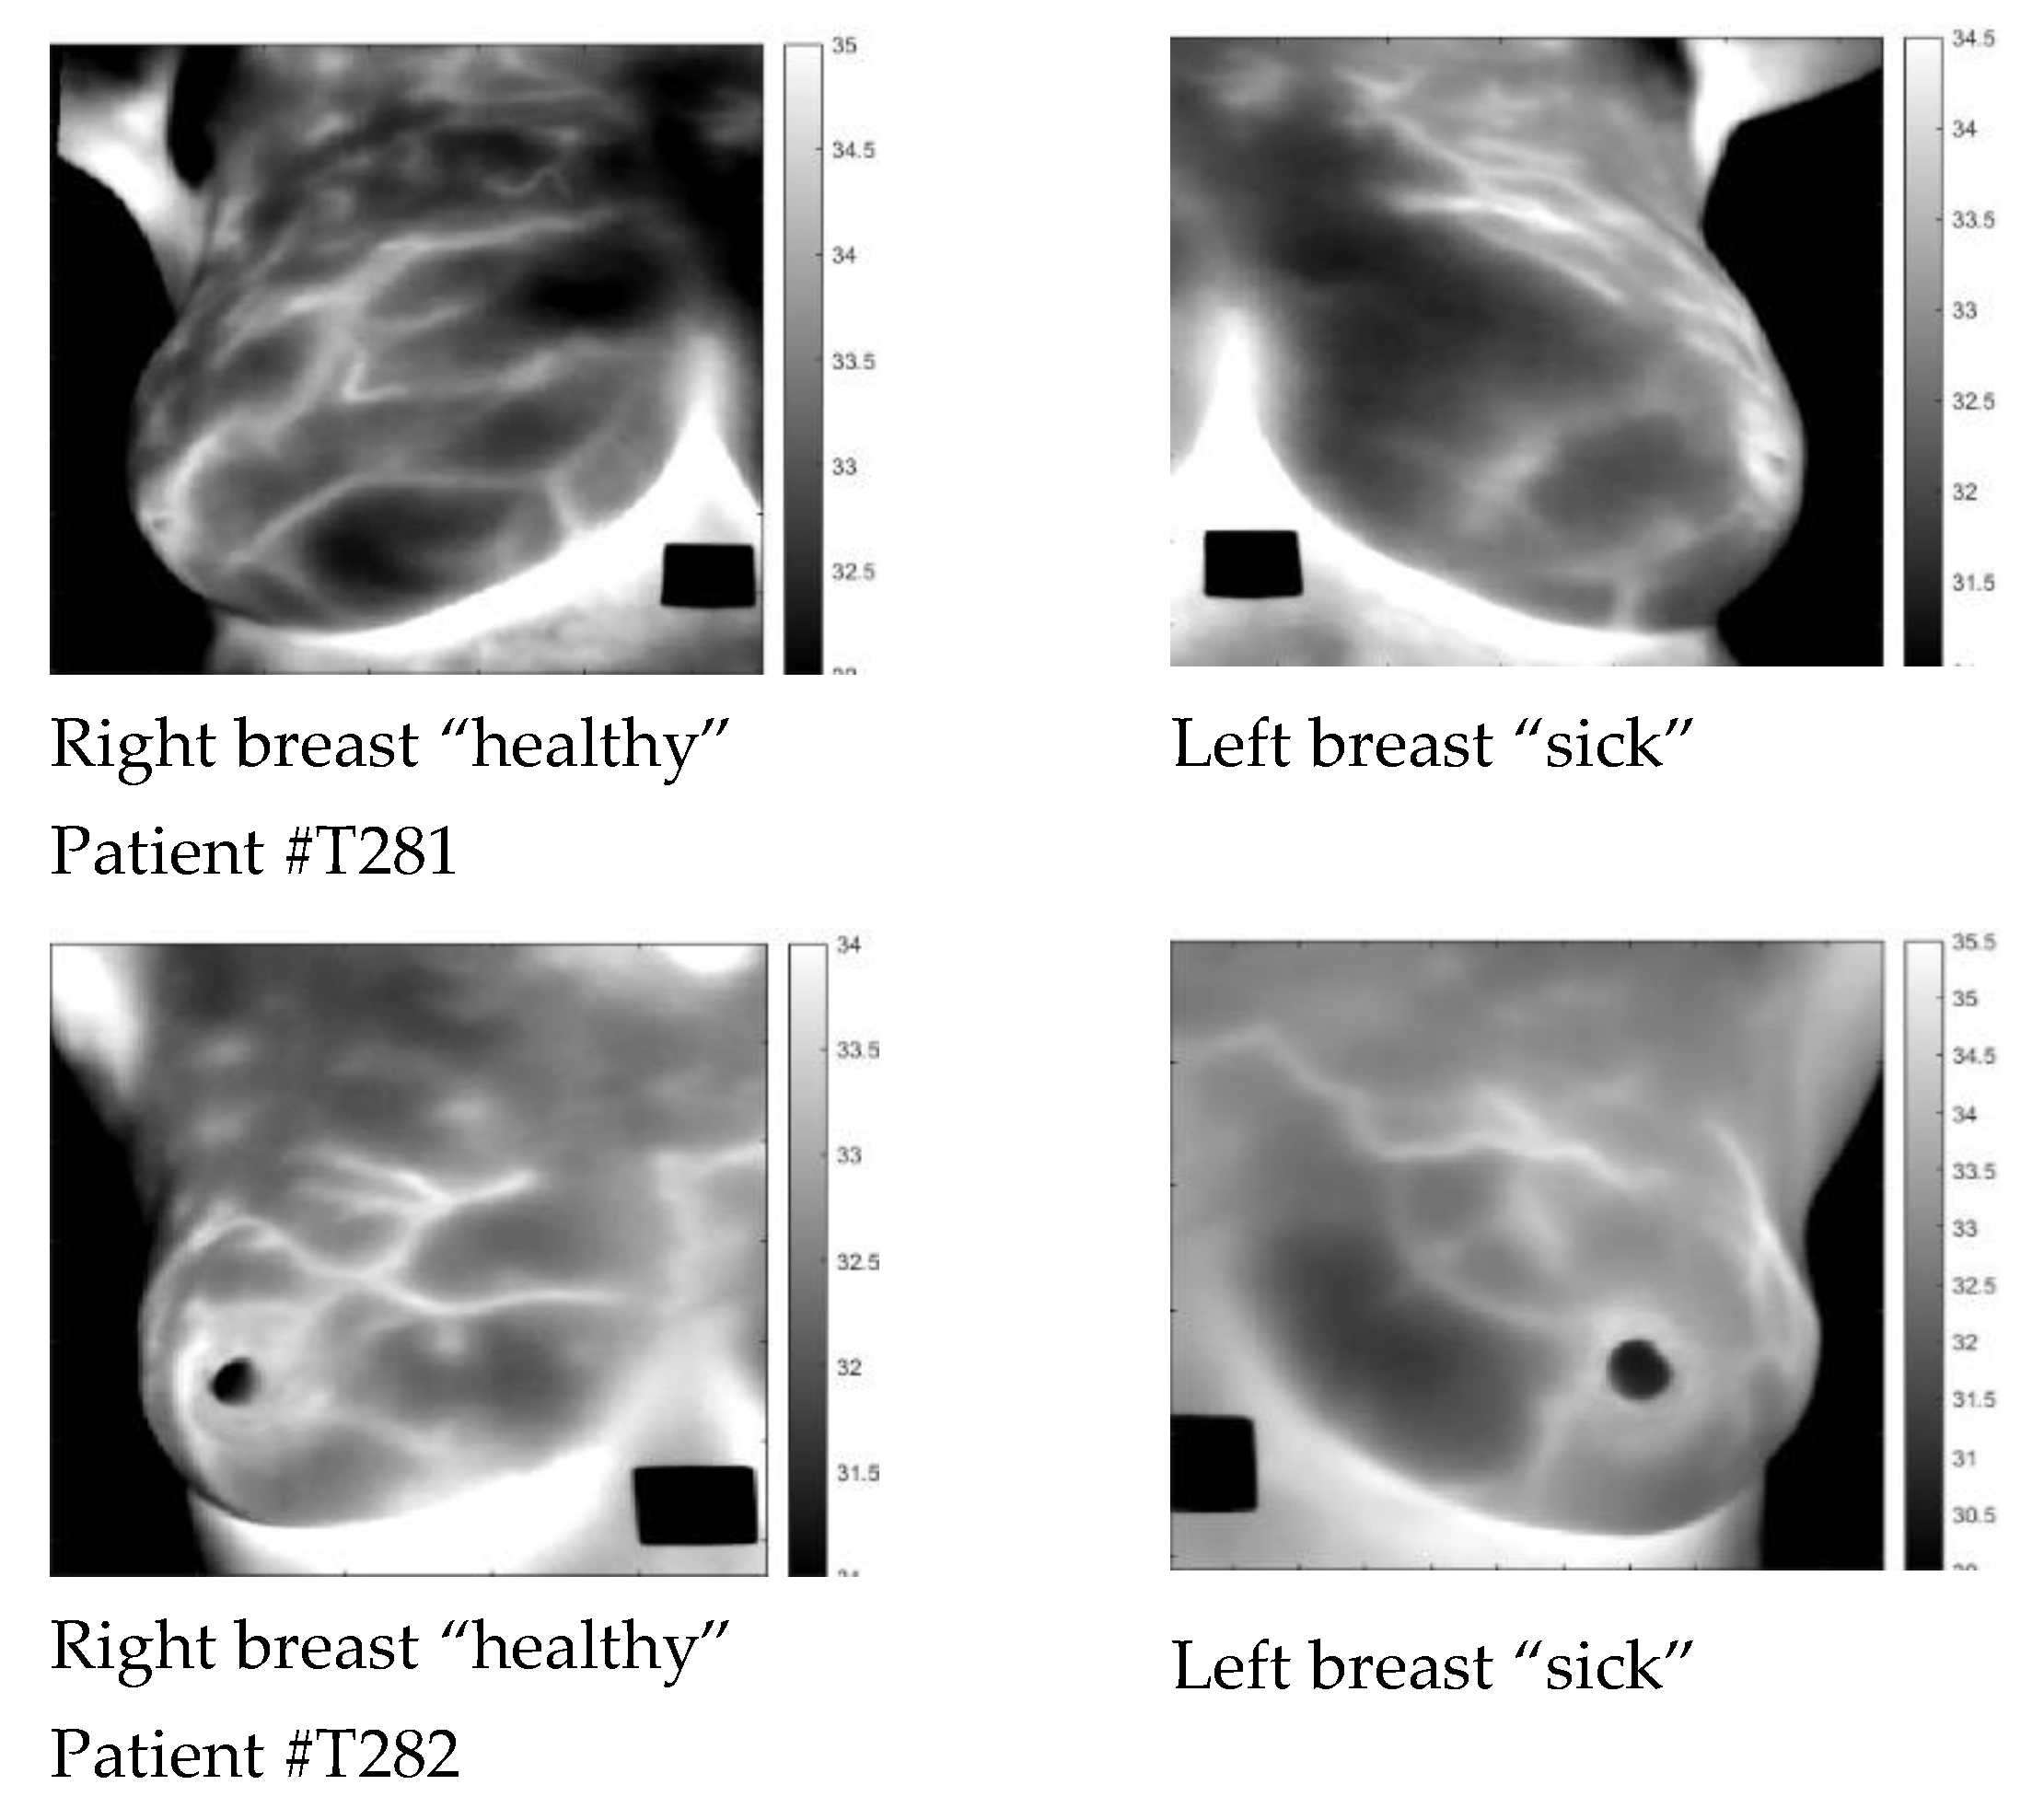

3.1. Data

| Patient | Age | Exam Details | Diagnosis | Quadrant | Biopsy | Complaint |

|---|---|---|---|---|---|---|

| T281 | 43 | Left | Sick | QSL | left | Pain in both breasts with burning |

| T282 | 46 | Left | Sick | QIM | left | Pain in both breasts |

| T285 | 57 | Right | Sick | QIL | right | Pain in the right breast |

| T286 | 50 | Left | Infiltrating Ductal Carcinoma | QSL | left | Itching in both breasts, secretion in the left breast |